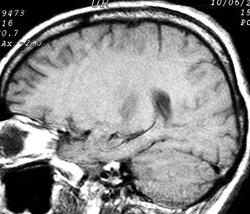

ГМ. Рассеянный склероз 2. +

Рассеянный склероз